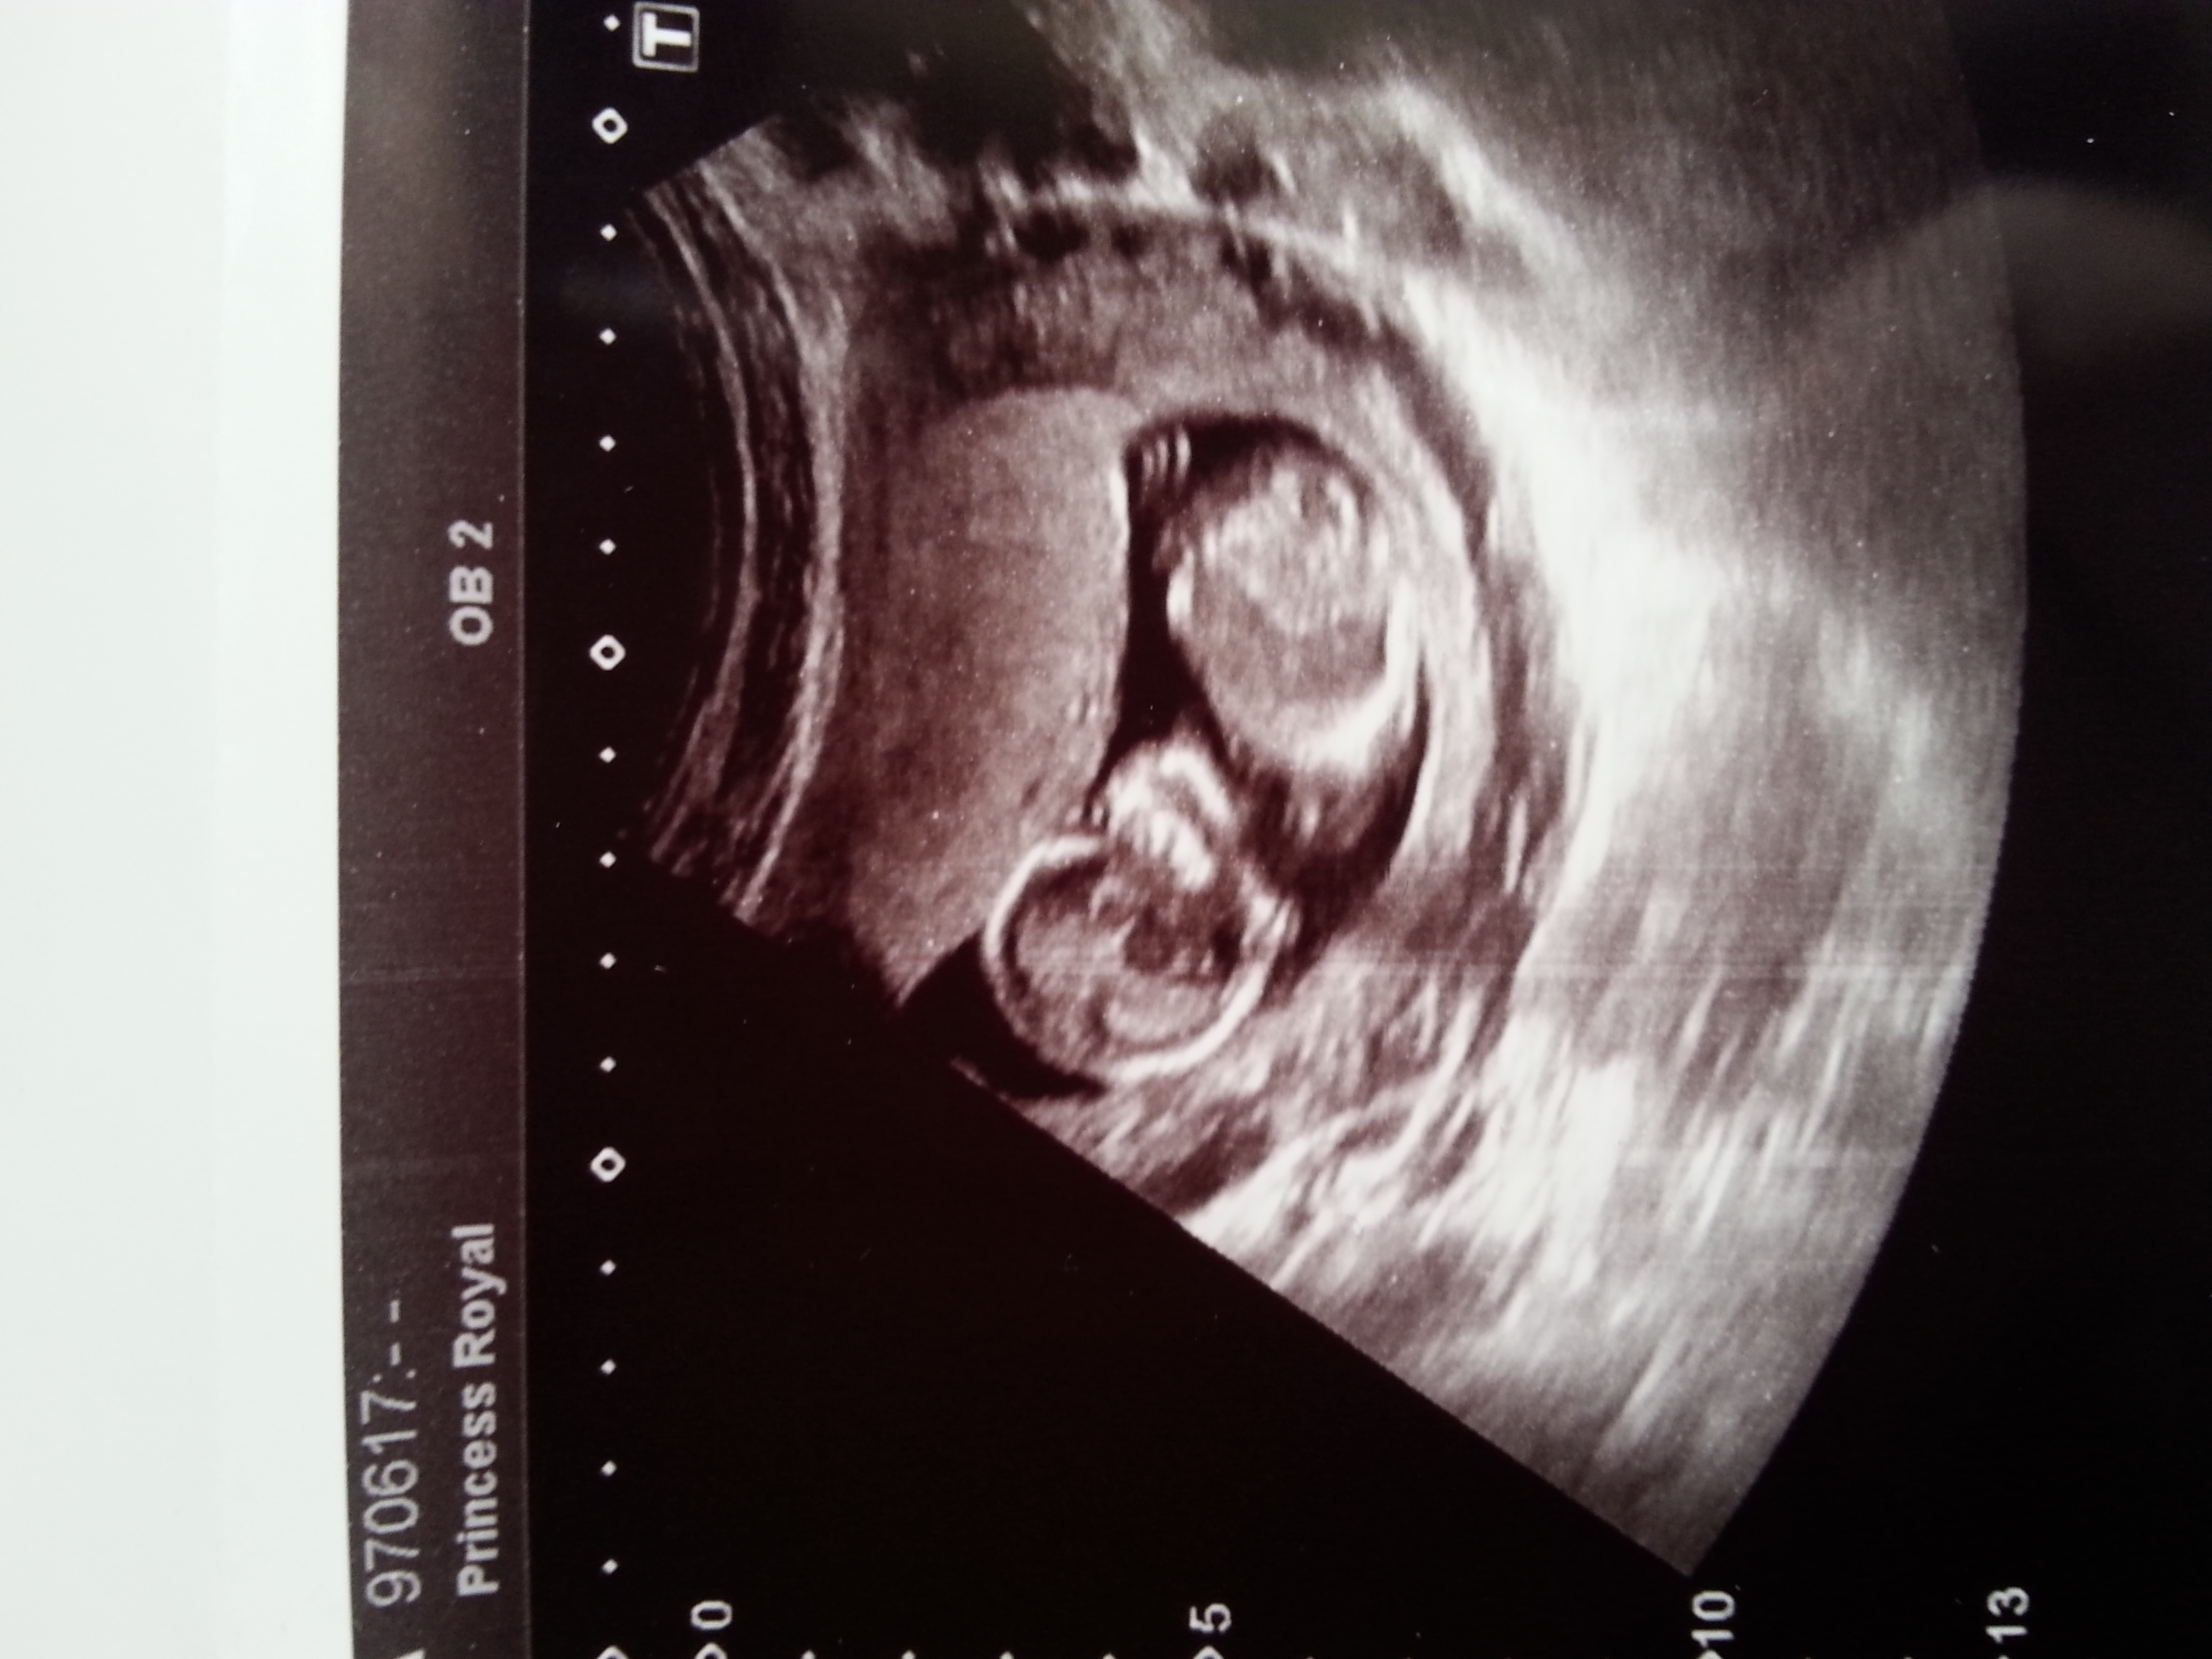

Gender guesses

Attachment 26867

Hello ladies, I had my nt scan today (baby was not cooperating so sadly no nub shot) but would anybody like to give me a guess? Based on vibes or skull? I know both those things are not reliable but its all in good fun :-) thank you.

If all in fun, I think I get a girly vibe from these. Not sure what from, though...

Yes all in fun :-) I didn't see anything at the baby's rump end which screamed boy at me so I'm still keeping my fingers crossed for a girl :-)